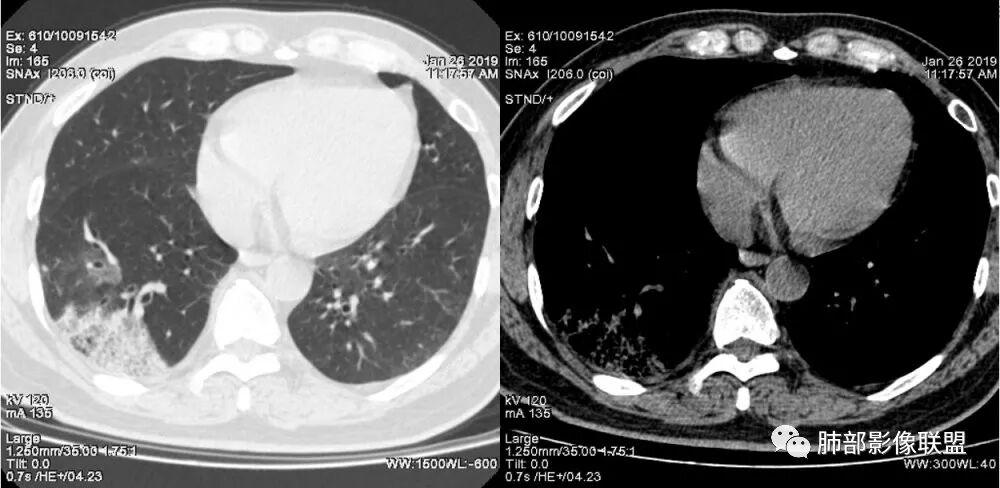

1.本例病灶较大片混杂密度影,胸膜下分布为主(未沿着支气管分布),该分布特点可见于大叶性肺炎、干酪性肺炎、淋巴瘤及粘液腺癌等。可惜未提供增强扫描图像。

2.病灶示中央实变区,周围GGO,可见明显小叶间隔增厚,GGO边界清楚,应当考虑到恶性病变的可能性。肺炎因炎性水肿及渗出,影像上边界常模糊不清,注意早期粘液腺癌可出现似清非清的边界。粘液腺癌因粘液成份较多,密度一般偏低,纵隔窗病灶常会消隐或范围会明显缩小,这不同于炎性实变。

3.病灶内支气管走形略显僵直,侧支少(粘液阻塞),也符合肺腺癌的枯树枝征。而大叶性肺炎的支气管是管壁光整、通畅、自然,结核的支气管常常壁增厚,甚至狭窄后扩张;

4.患者临床症状不重,临床炎性指标不高,结合肺内影像,应警惕肺炎型肺癌。

肺炎性肺癌,是一种影像学上表现为实变、斑片或大片状模糊阴影的肺癌。肺炎性肺癌影像表现不典型,是周围型肺癌的一种,病理类型多见于肺腺癌,少许见于鳞癌、小细胞肺癌,而肺腺癌中以粘液腺癌多见。

粘液腺癌是一种原发性肺腺癌的变异型,病理上起源细支气管壁以远的支气管与肺泡上皮,属于周围型;其细胞形态及排列方式与非粘液性腺癌有所不同,为成簇排列的粘液腺上皮,很早就有细胞内粘液及分泌细胞外粘液;早期粘液腺癌常为一单发结节,有沿气道距离播散的能力,中后期肿瘤细胞随粘液飘向更远的肺段及肺叶,会出现斑片状肌片状实变和/或磨玻璃密度样的肺炎样影像学改变;随着肺粘液腺癌体量的增大,粘液的播散,临床上会有咳白痰,查痰液脱落细胞会找到肿瘤细胞。